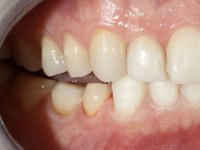

Paciente do sexo masculino, com 36 anos, não fumador. Fez tratamento ortodôntico e reabilitou esteticamente o sector anterior com restaurações em resina composta. As restaurações apresentavam um aumento vertical médio de 2 mm em relação o bordo incisal. Apresentavam-se esteticamente satisfatórias, mas com algumas fraturas incisais. O dente 1.5 apresentava um processo apical e o dente 2.6 apresentava tratamento endodôntico e uma lesão endo-periodontal. No maxilar inferior no local do dente 3.5 apresentava um implante com uma coroa aparafusada e o dente 8.5 ainda estava presente em boca com agenesia do dente 4.5. O paciente apresentava uma ligeira perda da dimensão vertical da oclusão provavelmente associada a um visível desgaste das superfícies oclusais. O periodonto era espesso e apresentava uma excelente higiene oral.

Após análise clínica e imagiológica foi proposto ao paciente recuperar a dimensão vertical da oclusão essencialmente à custa de incrementos oclusais inferiores utilizando “overlays” no sector posterior e facetas no sector anterior. A coroa aparafusada sobre o implante 3.5 seria substituída, no sentido de acompanhar este incremento. Na maxila o dente 2.6 teria extração indicada e posteriormente seria reabilitado com um implante e respetiva coroa. No sentido de reabilitar esteticamente o paciente duma forma minimamente invasiva, foi proposta a colocação de facetas feldespáticas no sector antero-superior. O objetivo de aumentar ligeiramente a D.V.O., teria como função “proteger” eficazmente o sector antero-superior.

Realizado o diagnóstico e tomada a decisão quanto ao tratamento a executar, tornou-se importante definir qual a sequência de trabalho a adotar no sentido de conseguir a reabilitação da D.V.O. (V.D.O), de forma progressiva e equilibrada. Na primeira fase fez-se uma pré-impressão da arcada inferior com silicone tipo “putty” e em seguida realizou-se o preparo dentário de todo o sector posterior. O preparo para os overlays foi feito coronalmente à linha amelo cementaria no sentido de ser o mais conservador possível. A impressão foi feita com técnica de dupla mistura após afastamento gengival realizado com pasta de caulino. A provisória foi realizada com resina composta de polimerização dual. Em laboratório foram realizados os overlays após se ter aberto ligeiramente (1,5mm) a D.V.O. nos modelos montados em articulador semi-ajustável. Simultaneamente o sector antero-inferior foi encerado no sentido de acompanhar este aumento da D.V.O. Também foi confecionada uma chave de silicone translucido para posterior confeção dos provisórios antero-inferiores. Em boca foi primeiro realizada a provisionalização dos dentes anteriores utilizando resina composta previamente aquecida após preparação das superfícies dentárias para a adesão. Foi colocado o dique de borracha para promover o isolamento absoluto e posteriormente foram colados os overlays. Em laboratório foi realizada nova chave de silicone para confecionar os provisórios antero-superiores. Seguidamente em boca foram preparados os seis dentes antero-superiores após colocação do fio de afastamento gengival. Feita a preparação adequada das superfícies dentárias foi realizada a impressão com técnica de dupla mistura e a respetiva provisória. Em laboratório foram confecionadas 6 facetas feldespáticas num modelo de trabalho tipo “Geller”. A provisória foi removida e as facetas foram coladas em boca utilizando um isolamento relativo competente. Esta opção foi tomada em virtude de uma prévia experiencia negativa com a colocação do dique de borracha na mandibula. Após a colagem dos laminados antero-superiores foram dadas 12 semanas para avaliar a adaptação do paciente à nova situação e então iniciar a confeção das facetas antero-inferiores. Após colocação do fio de afastamento gengival. foram feitos os preparos dentários adequados e em seguida foi feita a impressão. Também foi feita a preparação do dente 3.4 que, entretanto, tinha sofrido uma fratura do overlay. As facetas e a restauração do 3.4 foram realizadas num modelo de trabalho tipo “Geller”. Após remoção da provisória, as facetas foram coladas em boca, utilizando um isolamento relativo pelas razões apontadas anteriormente. Após colocação do trabalho o paciente foi reabilitado por outros colegas com um implante na zona do 2.6 e substituição da coroa aparafusada sobre o implante colocado no local do 3.5. Posteriormente surgiram fraturas nos overlays dos dentes 4.7 e 3.7 que foram reabilitados com overlays em Zr.